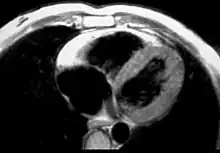

MRI in a patient affected by ARVC/D (long axis view of the right ventricle): note the transmural diffuse bright signal in the RV free wall on spin echo T1 (a) due to massive myocardial atrophy with fatty replacement (b).

Fatty infiltration of the RV free wall can be visible on cardiac MRI. Fat has increased intensity in T1-weighted images. However, it may be difficult to differentiate intramyocardial fat and the epicardial fat that is commonly seen adjacent to the normal heart. Also, the sub-tricuspid region may be difficult to distinguish from the atrioventricular sulcus, which is rich in fat.

Cardiac MRI can visualize the extreme thinning and akinesis of the RV free wall. However, the normal RV free wall may be about 3 mm thick, making the test less sensitive.